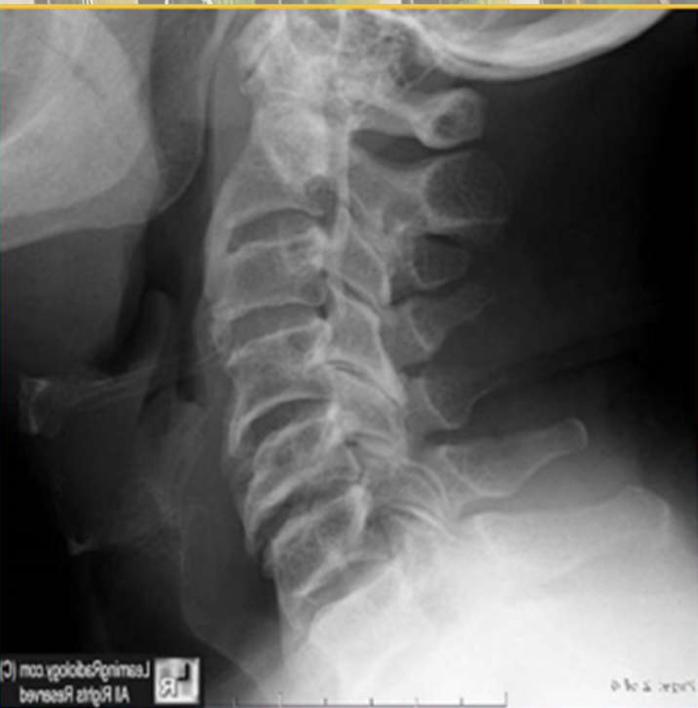

What three DDx could you give this patient

OPLL

AH

OA/DDD